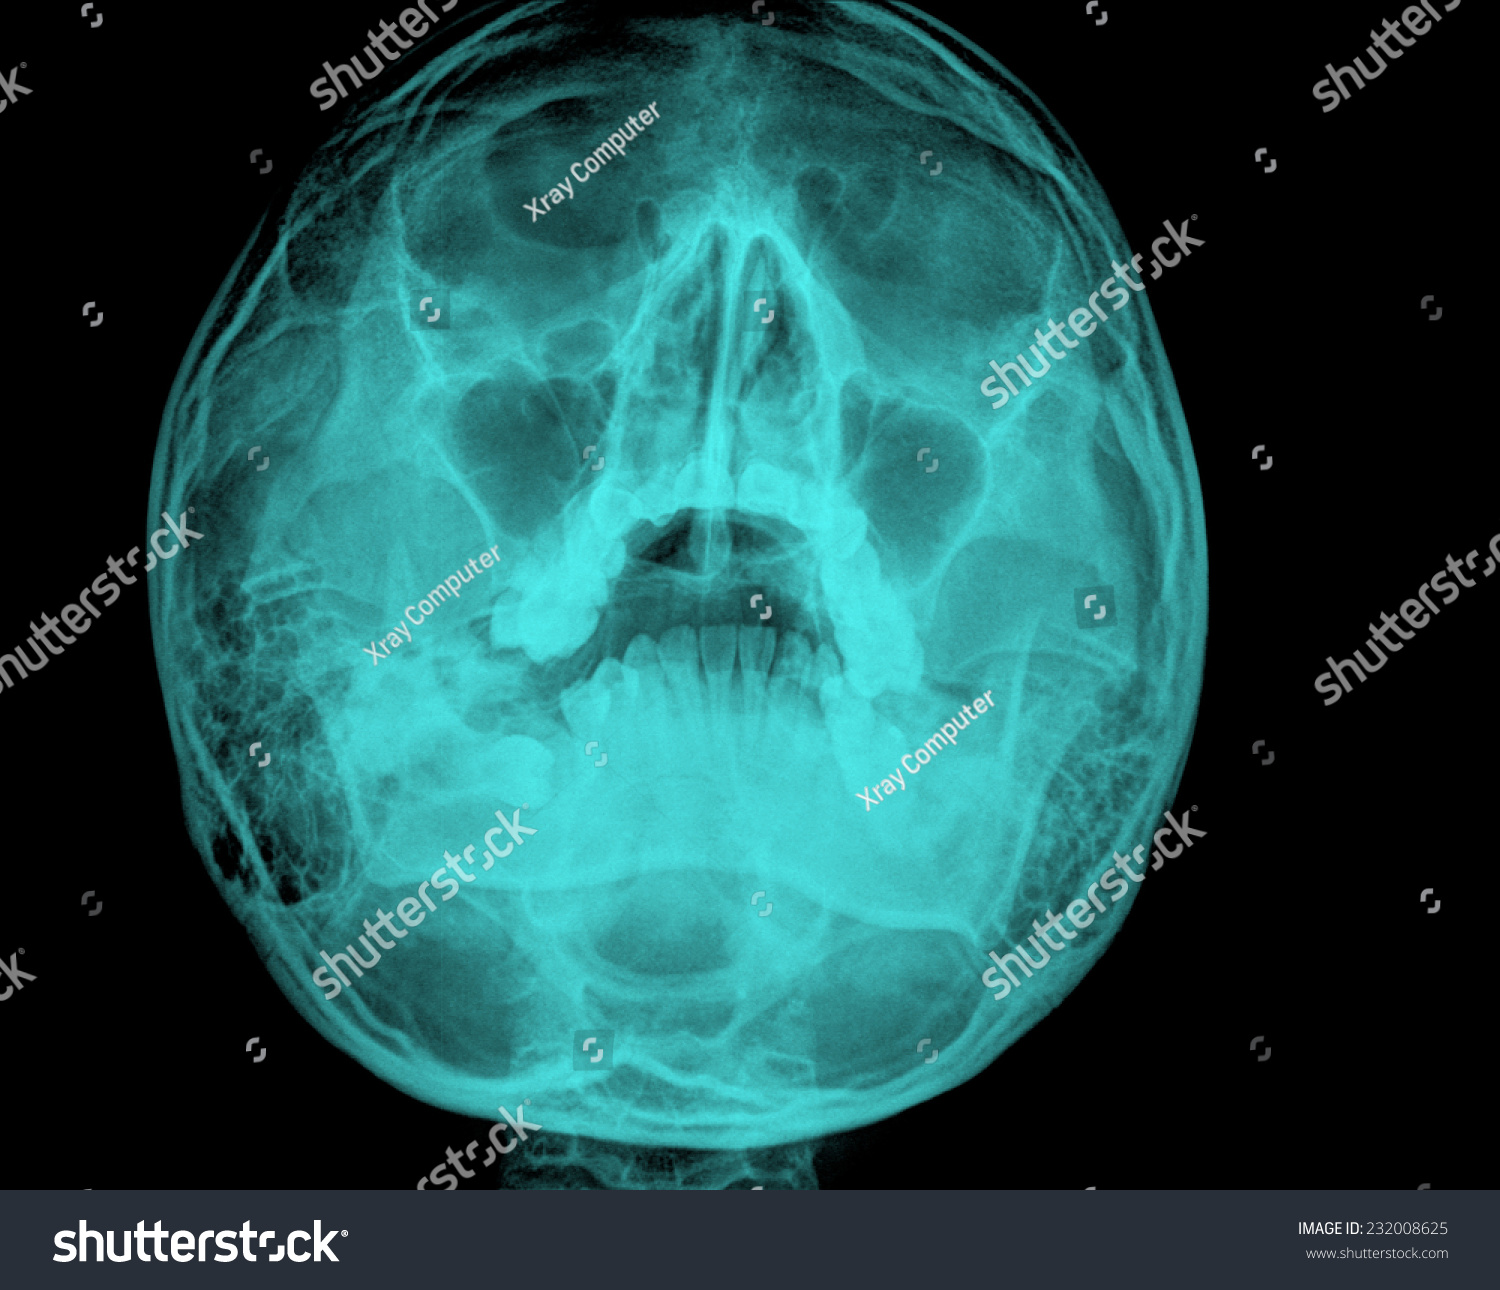

Prepare to be captivated by List, a showcase of real human skull front view black and white imagery powered by ieltschampions.edu.vn. More related visuals are below.

real human skull front view black and white

Posts: real human skull front view black and white